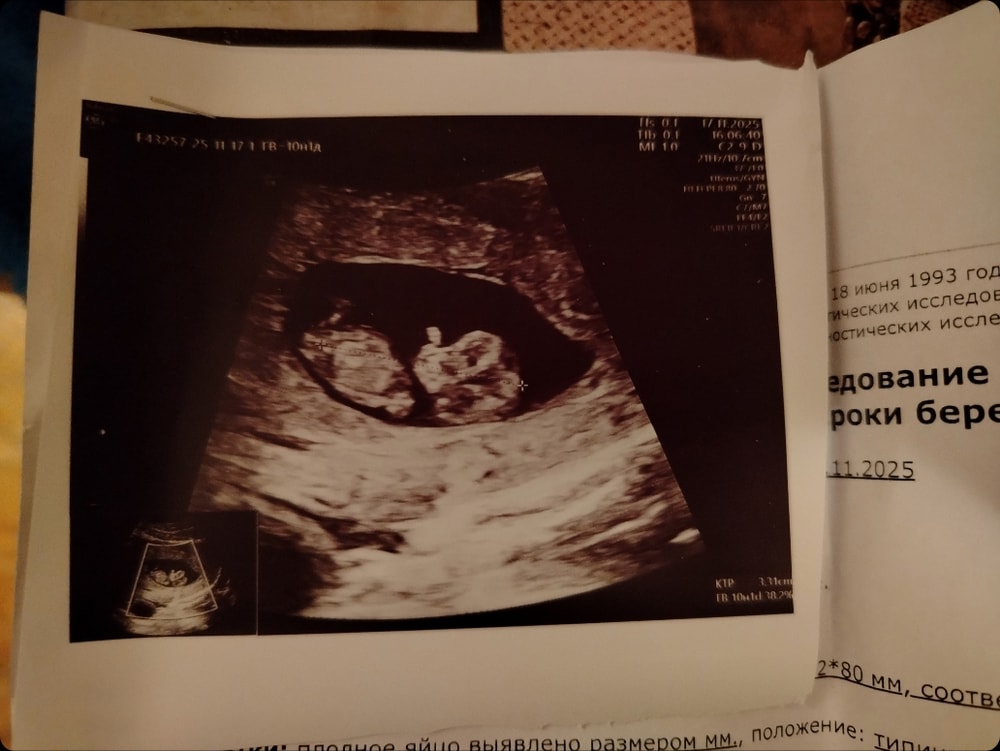

Это срок по М, но я уверена, что срок около недели меньше.

Ктр 21

Свд 44

Миома 10см на 9 см

Желточный меш 3.5

Хорион 6.5

Сб +

ПЯ вытянутой формы???? О чем это говорит??

Предлежание хориона

У меня 23.10 обнаружили ретроохориальную гематому размером 20 *15 мм, через неделю гематома увеличилась 39*17мм, отправили в стационар, 5.11 выписали с гематомой 22*26*24 мм 7,6 мл объем ( смотрели через живот на узи), сегодня пошла на узи гематома размером 31*14*32 объем 7,23 мл ( смотрели вагинальное).